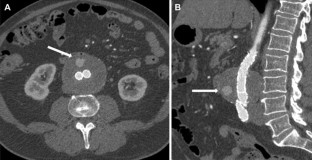

Fig. 3